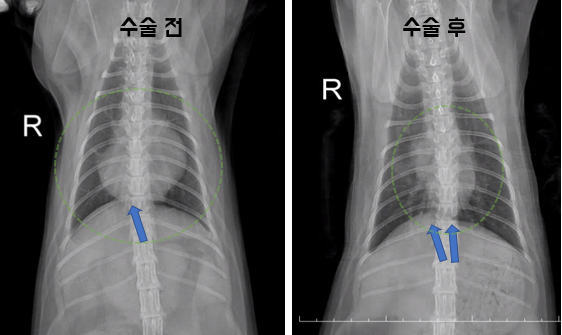

곧바로 수술에 들어간 헬릭스 동물메디컬센터 의료진은 제자리를 잃고 흉강 내로 밀려난 장기를 복강으로 옮긴 뒤 손상된 횡격막과 결손 부위를 복구하는 수술을 통해 성공적으로 마무리할 수 있었습니다.

수술이 끝난 후 재촬영한 X선 검사 결과 제자리를 찾지 못하고 밀려나던 장기가 제자리로 돌아온 모습을 확인할 수 있었습니다.